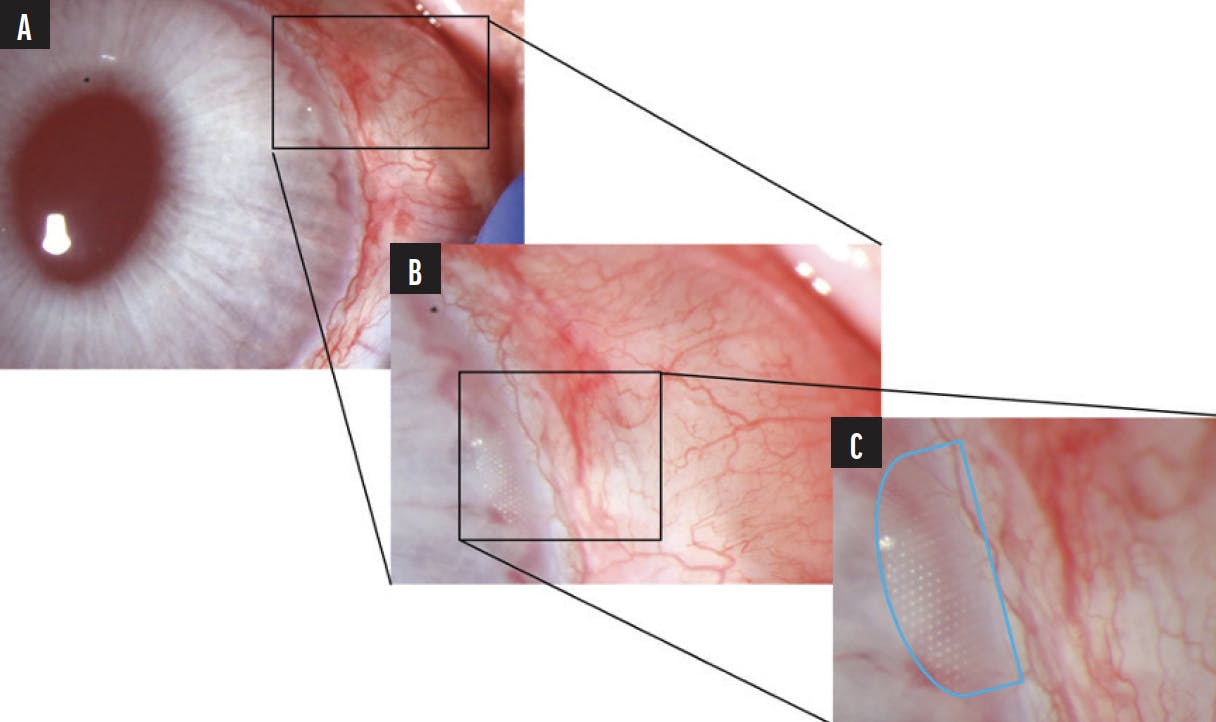

VisiPlate is undergoing early feasibility testing and has been evaluated in multiple long-term (3–6 month) studies using New Zealand white rabbit eyes. In this rabbit model, VisiPlate has been shown to be well tolerated and to reduce IOP.3 The tip of the VisiPlate is positioned in the anterior chamber (Figure 2), where it facilitates aqueous flow through the network of hexagonal microchannels into a low-lying bleb. The bleb has been confirmed with a postoperative injection of fluorescein dye into the anterior chamber, which revealed dispersion to the subconjunctival space (Figure 3). The company continues to validate the performance of VisiPlate in rabbit models, and testing has shown healthy bleb development even without the use of an antifibrotic agent such as mitomycin C.

Figure 2. A depiction of VisiPlate in a New Zealand white rabbit model with progressive magnification. A low-lying bleb developed at day 90 without mitomycin C (A). The semitransparent tip of the VisiPlate is visible within the anterior chamber (B). The VisiPlate tip with visible hexagonal microchannels is outlined in blue (C).